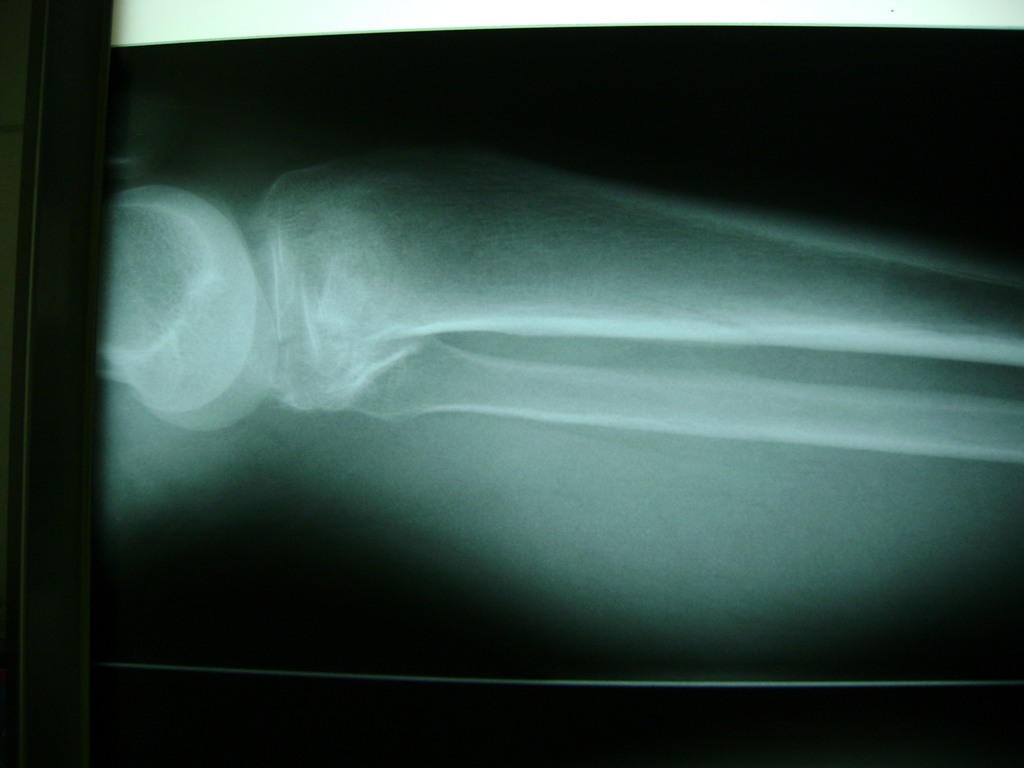

Cirugías de Húmero - Rodilla